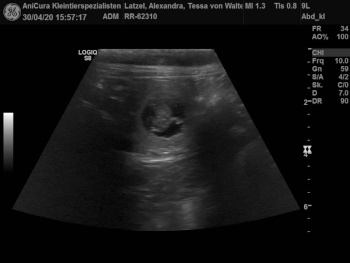

Aennchen und Tessa sind Schwanger! Hier sind die Ultraschallbilder !!! |

| Die Ultraschallbilder von Tessa von Waltenweiler!!! |